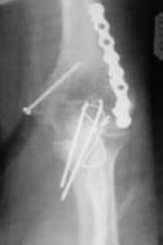

Подскажите пожалуйста, как можно в дальнейшем этому больному помочь. В марте первая

операция, пришлось оперировать на 16 сутки в виду инфицированных садин и анемии. Заживление

первичным натяжением, ранняя разработка после операции, а через 2 нед болевой синдром,и

постепенно движения в локтевом суставе ограничились до полного анкилоза. Повторно через 4

месяца вторая операция - артролиз, удаление оссификатов, удаление фиксаторов,

реостеосинтез этой же реконструкционной пластиной и винтом. Интраоперационно после

удаления оссификатов и фиксаторов обнаружил, что переломы не сросшиеся, поэтому пришлось

синтезировать заново. Зажила рана первично, объем движений в локтевом суставе сгибание 70,

разгибание160, ротационные движения востановились полностью, вроде бы успокоились.

Опять постепенно в течении 8 нед после повторной операции постепенно движения ограничились

до 80 - 110, на снимке оссификат. Снимки во вложении, буду рад Вашим советам. Спасибо!